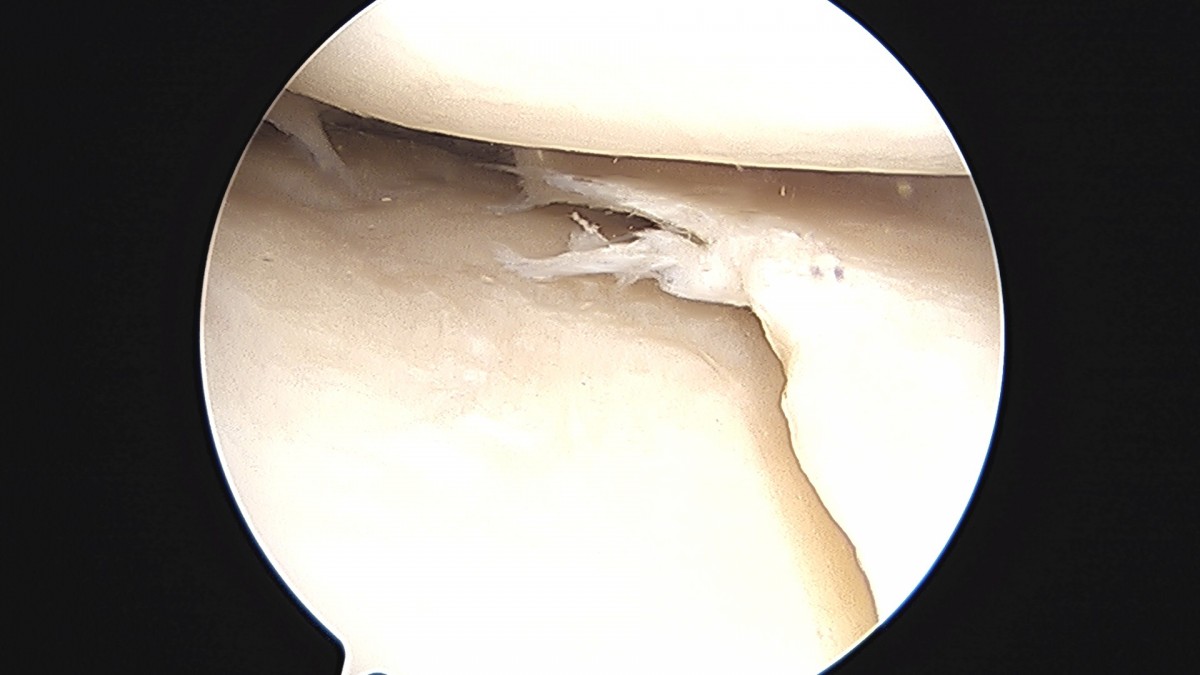

이재상원장님 무릎 반월상 연골판 절제술 강일O 환자

dae765e4d9ac96aee867c9d6292d8784_1758006723_1811.jpg